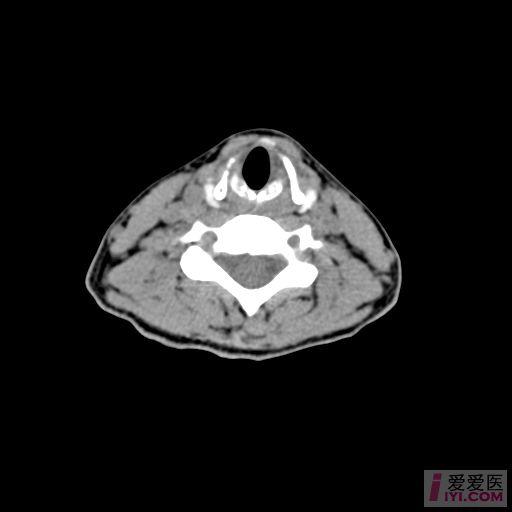

ct50855:左侧扁桃体区是什么啊?

ct平扫示口咽部外形不对称,左侧扁桃体区可见形态不规则软组织肿块.